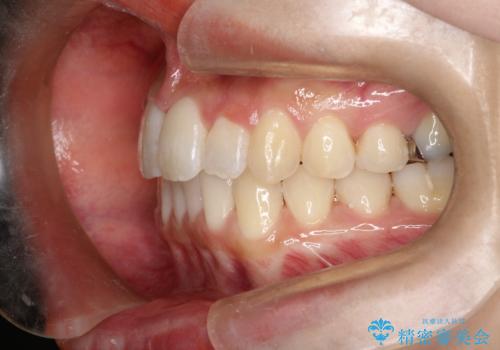

- 前歯の正中離開の改善を希望され来院された患者様です。

初診時の歯並びの状態としては、上下ともに前歯部の中等度のがたつきがあり、特に左上の前歯が1本内側に入り込んでしまっている状態でした。

また、2mm程度の正中離開がありました。

抜歯なし/インビザラインによるマウスピース矯正にて治療を行いました。

内側に入り込んでしまっている歯を出してくることに非常に時間がかかりましたが、一度歯を歯茎の方へ押し込みそして前へ出してくる2段階の治療を行いました。

見た目、噛み合わせ及び、治療期間や施術内容に大変ご満足いただきました。